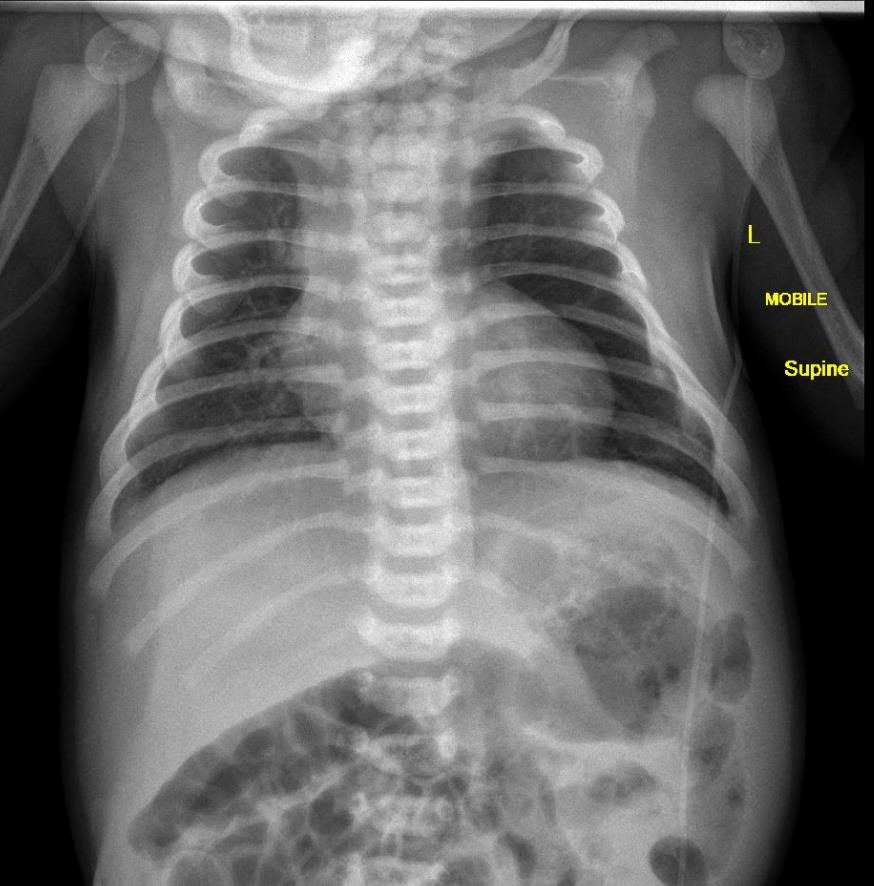

Рентгенография выявляет следующие признаки транспозиции магистральных сосудов:

Кардиомегалия за счёт дилатации правого желудочка, проявляющаяся расширением сердечной тени преимущественно вправо и увеличением кардиоторакального индекса.

Характерная конфигурация сердечной тени в виде «яйца на боку» с узкой сосудистой ножкой из-за переднезаднего расположения магистральных сосудов.

Усиление лёгочного сосудистого рисунка с выраженным увеличением прикорневых сосудов вследствие гиперволемии малого круга кровообращения.

Нормальные или уменьшенные размеры дуги аорты, расположенной атипично — справа или по средней линии, фиксируемые в прямой проекции.

Выбухание лёгочной артерии и расширение её ствола на фоне уплощённых контуров аорты, хорошо различимое в боковой проекции.